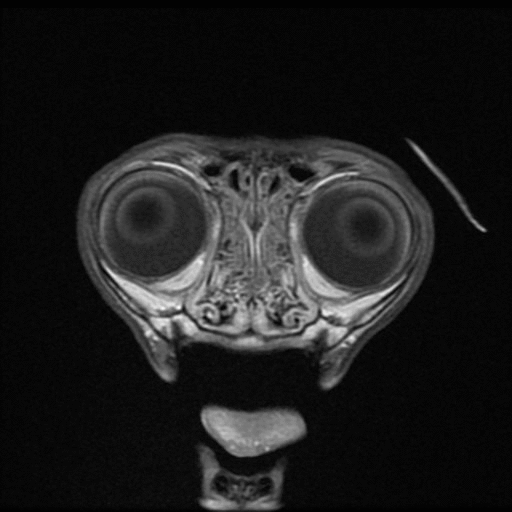

Meningiomas are typically benign and slow growing tumors arising from the meninges. They are commonly well encapsulated, focal, round, and solid. Less commonly, meningiomas can be invasive, have plaque-like shapes, or varied internal composition. They can occur anywhere along the CNS, but are most common around the brain. Meningiomas have a few key identifying characteristics; some or all may be present: